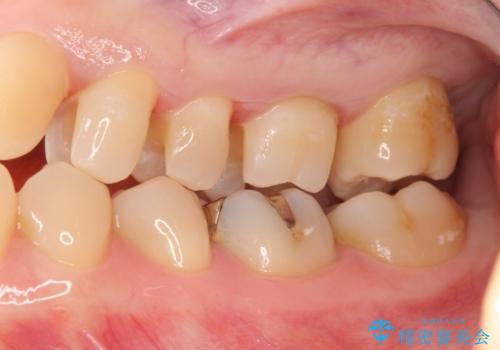

3本仮づめのまま放置 セラミックインレーへ

- 他院で治療途中で放置したところを治療したいとご来院されました。

仮づめはフロスもできないため、不潔になりやすく長期的には虫歯になりやすいです。

目立たない白いものがご希望とのことで、セラミックインレーで修復しました。

仮づめの状態でしたが、そこまで中は虫歯になっておらず、神経の治療も不要でした。